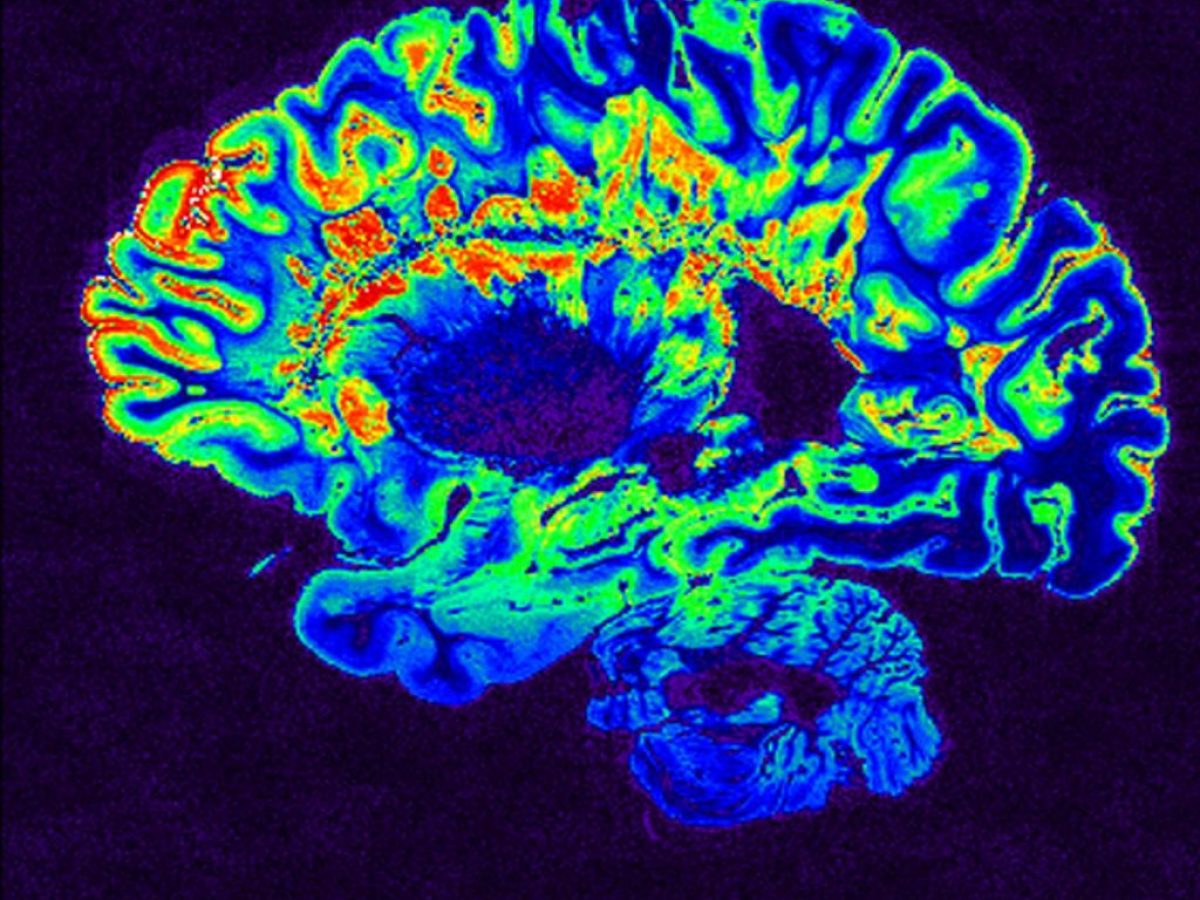

Η σκλήρυνση κατά πλάκαςΚάνε εγγραφή στο κανάλι μας στο YoutubeΓίνε μέλος στο κανάλι μας στο Viber– Σε ένα από τα δύο σημεία να υπάρχει ενεργός σύνδεσμος